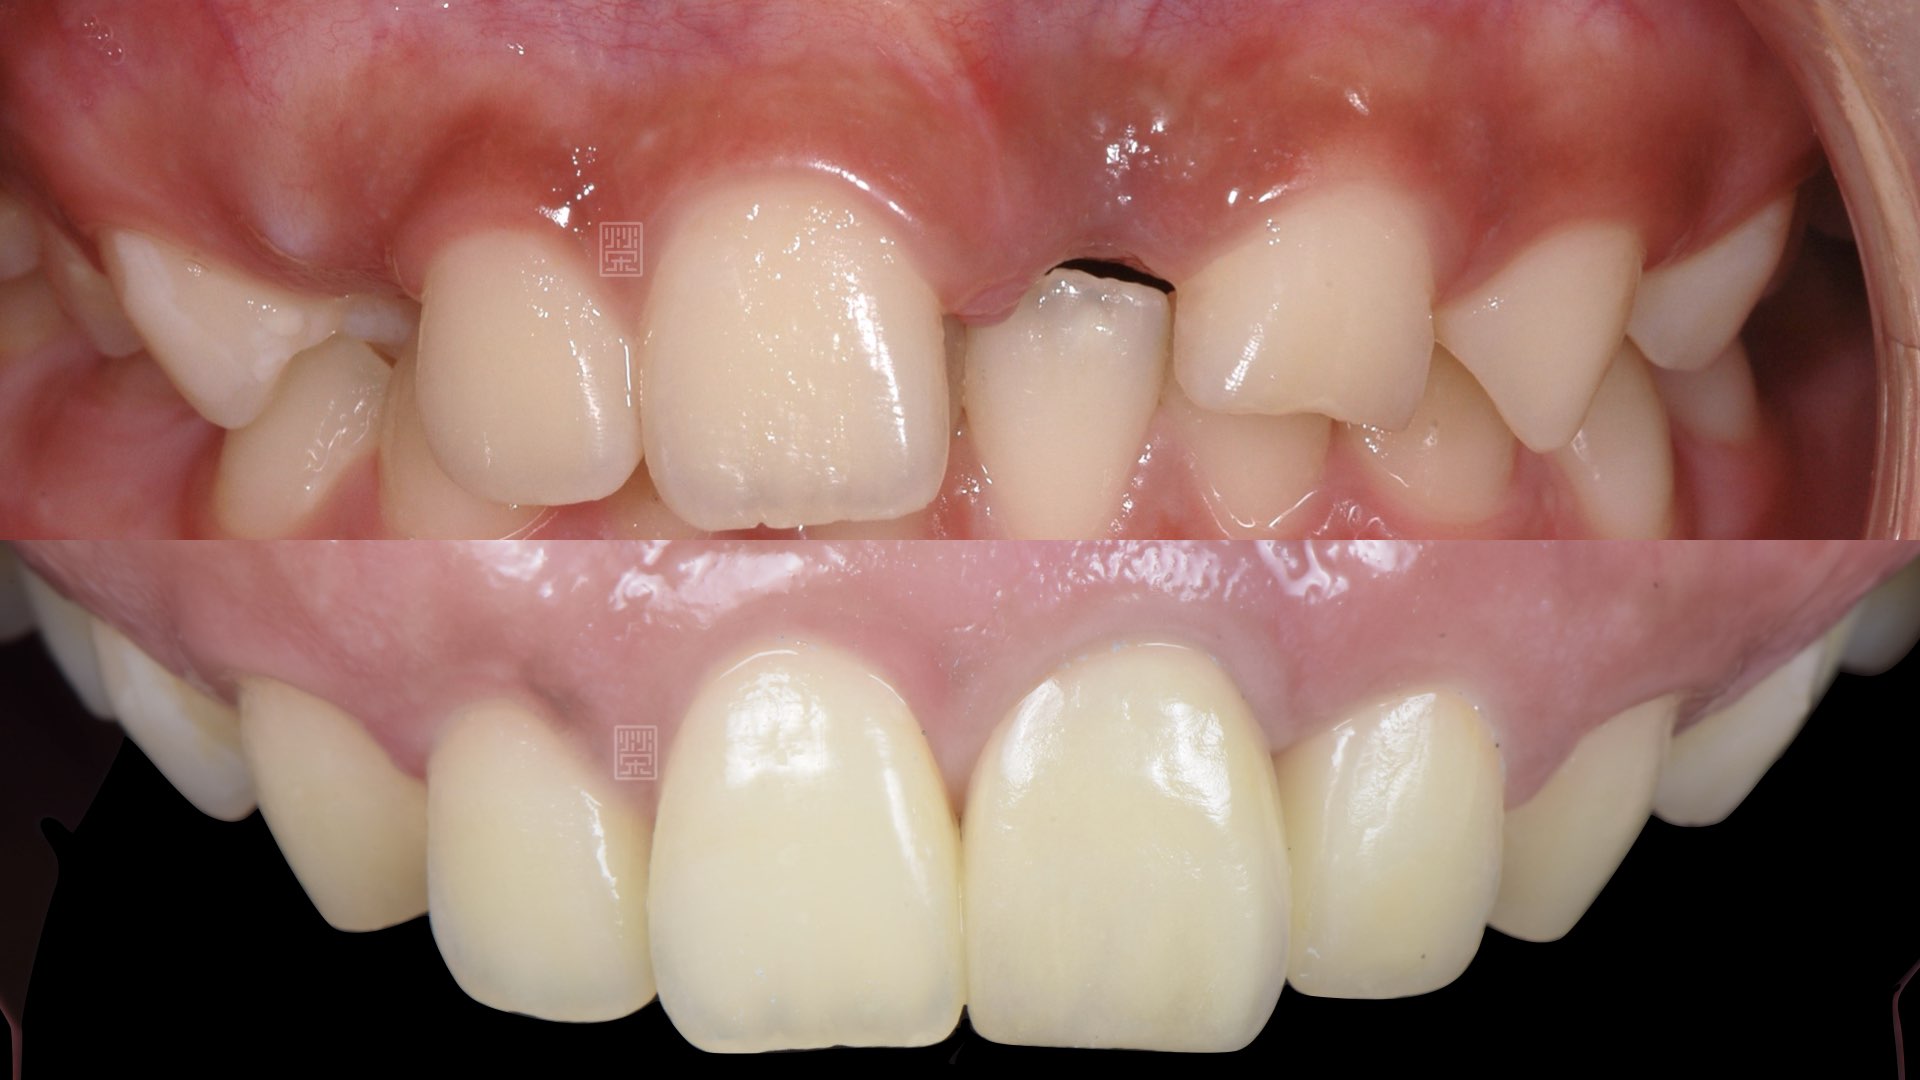

2011年,門診來了一個小學四年級小朋友,因為意外把中門牙撞飛了,因考慮發育過程與寬大的牙髓神經,許多治療受到限制,當下決定用馬利蘭牙橋先維持外觀,也告知家長,因為接下來小孩發育、咬合位置會有變化,可能一陣子會有牙橋脫落的機會,但主要可以減少對牙齒的傷害,約等到十八歲成年後再來評估較穩定的治療。

小學時門牙撞飛

治療十二年後馬利蘭牙橋